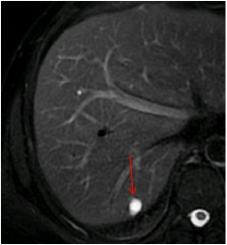

病例:肝囊肿,女性,40岁,B超体检发现肝占位,磁共振腹部成像清晰显示肝内占位病灶为囊肿(箭头)。

除了可以为超级肥胖的患者提供足够的检查空间外,大孔径甚至可以为这些患者提供侧方摆位!这可以解决他们仰卧呼吸困难的问题。